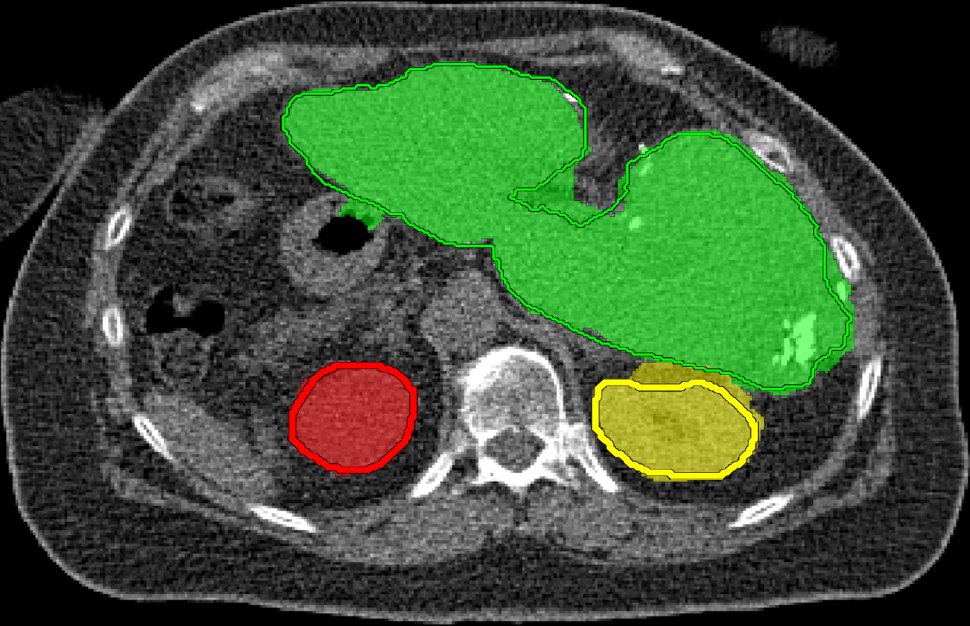

We applied our method on PET-CT scans of three different subjects to segment their liver, left kidney, right kidney and the background. Although we applied our method and Potts model on the 3D volumes we only show the results on a few representative slices from each volume in Fig.11. Also, the results of different methods for each subject were computed using the same smoothness. We can see from the last two rows which compare our method to Potts, using Hedgehogs constraints enabled us to avoid geometrically incorrect segmentations, e.g. one liver inside the other (last-row middle), or parts of left kidney is between the right kidney and liver (last-row right). Furthermore, for test subjects 1 and 2 the kidneys and background were poorly segmented by Potts model, e.g. most of the kidneys were segmented as background for test subject 1. Potts poor performance is due to the large overlap between the kidneys and background color models. This overlap resulted in an in-discriminative data term for Potts to properly separate them. This issue becomes worse in iterative frameworks where color models are re-estimated based on current segmentation. To be specific, if at any iteration Potts model resulted in a bad segmentation then re-estimating the color models will bias them towards the bad segmentation and subsequent iterations worsen the results. Comparing our results for subjects 1 and 2 to Potts model shows that our method is less prone to the aforementioned issue as we forbid undesirable segmentations, i.e. those that do not respect shape constraints.

| Subject 1 | Subject 2 | Subject 3 | |||

| Our method (Hedgehogs Shapes + Potts) | ![]() |

![]() |

||

|||

| \rdelim}1910pt Same Slice | |||||

|

Potts |

For quantitative comparison, Table 1 lists for each organ of a subject the Score, Precession and Recall measures of our method and Potts model where For the kidneys, our method clearly out performed Potts model, e.g. note Potts model poor precision/recall for subjects 1 and 2. For the liver, both methods performed comparably.